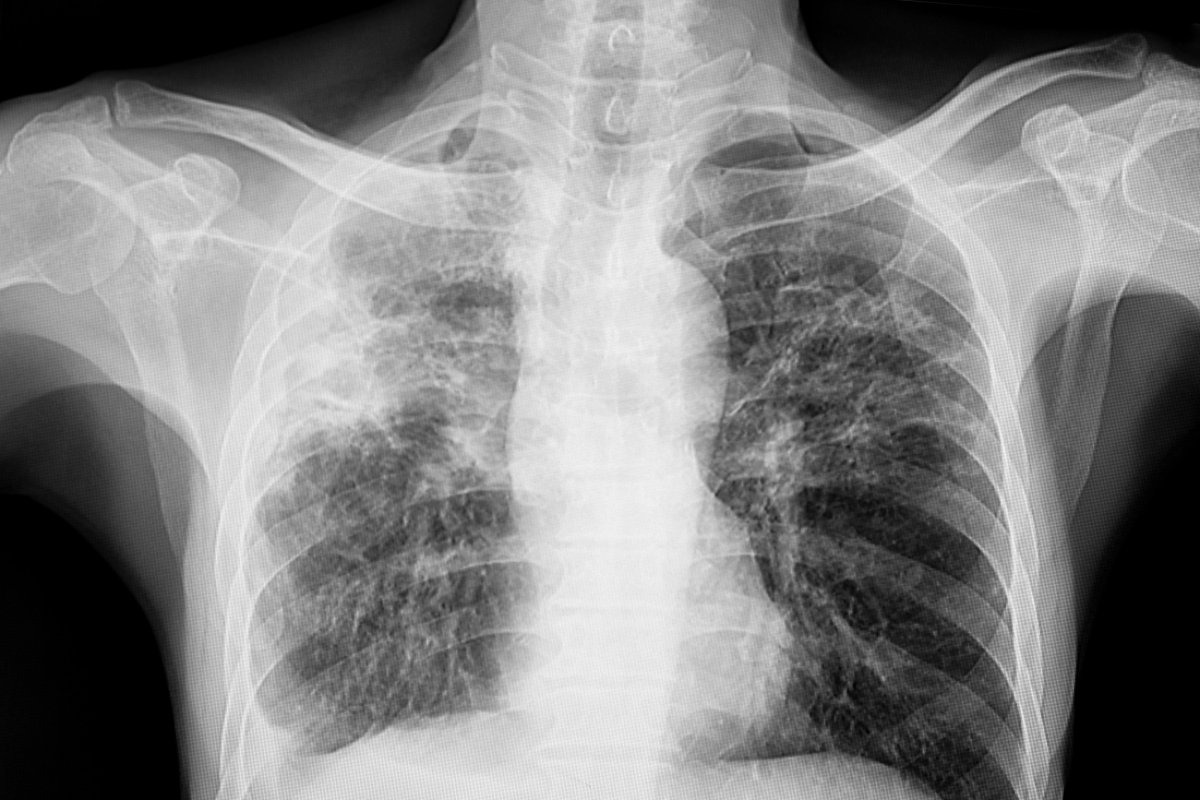

Progression to Pneumonia

Untreated bronchitis can turn into pneumonia. Pneumonia is a serious infection that inflames the lungs’ air sacs. It can fill these sacs with fluid. People with bronchitis are more likely to get pneumonia, says doctors, if they are older or have other health issues. “Pneumonia is very dangerous, mainly for the elderly and young kids,” say health experts.

Respiratory Failure

Untreated bronchitis can also cause respiratory failure. This is when the blood’s oxygen level drops too low or carbon dioxide levels rise too high. This is more common in those with chronic bronchitis or lung problems. Respiratory failure is a serious emergency that needs quick help.